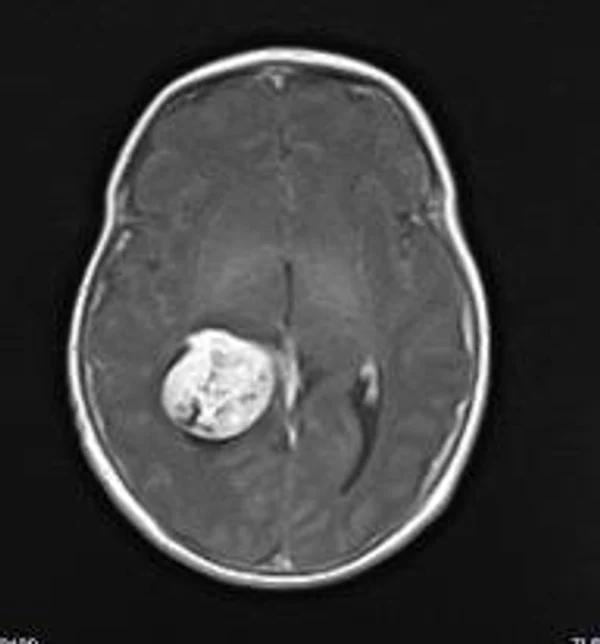

В качестве примера приведены 2 случая хирургического лечения новорожденных с врожденными опухолями головного мозга и позвоночного канала. У новорожденной девочки опухоль (хориодпапиллома) располагалась в области треугольника правого бокового желудочка (рис. 28 а, б). В возрасте 2-х недель жизни опухоль удалена. По данным МРТ головы с внутривенным введением контрастного препарата выполненной через 2 дня после операции опухоль удалена тотально (рис. 28 в). Послеоперационных осложнений не наблюдалось. У второго пациента 2-х нед. жизни врождённая опухоль (нейробластома) располагалась в позвоночном канале на уровне Th10-L3 позвонков (рис. 29 а) и распространялась в забрюшинное пространство. Клиническая картина заболевания складывалась из нижнего вялого парапареза и нарушения функции тазовых органов. Во время операции остистые отростки Th 11-L3 позвонков рассечены по средней линии. Дужки 6 данных позвонков надломлены и разведены в стороны. Опухоль располагалась экстрадурально, отделена от дорзальной поверхности дурального мешка и корешков спинно-мозговых нервов, после чего полностью удалена из позвоночного канала. Половинки дужек позвонков сведены к средней линии и сшиты между собой. Опухолевый узел в забрюшинном пространстве через 2 нед. удален онкологами. Через год после операции по данным МРТ рецидива опухоли нет (рис. 29 б). При спондилографии дефектов задней стенки и деформаций позвоночника не выявлено (рис. 29 в). Мальчик ходит, мочу и кал удерживает.